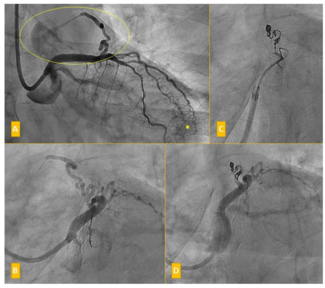

A 47-year-old male lifelong smoker underwent percutaneous coronary intervention (PCI) to the distal segment of an ectatic right coronary artery (RCA) in the context of non–ST-elevation myocardial infarction (NSTEMI). The procedure was...